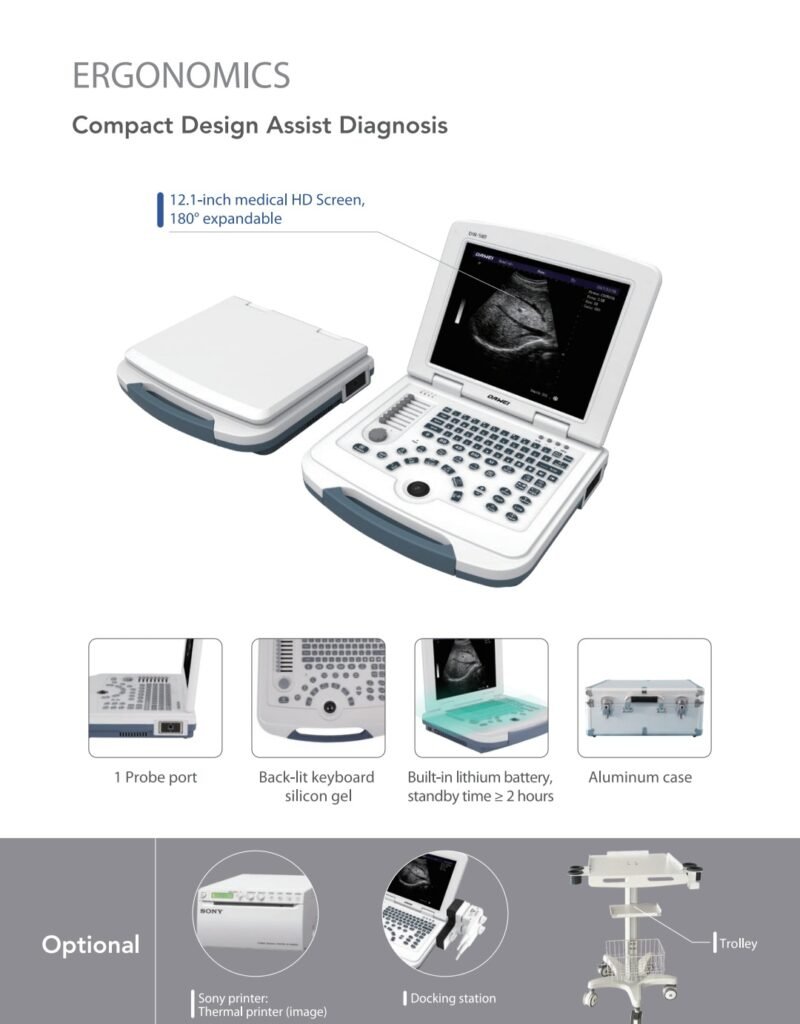

The DW-580 features a 12.1-inch medical-grade HD display that’s 180° rotatable, ensuring optimal viewing angles during examinations. Its laptop-style structure makes it easy to transport and operate in various clinical settings, including mobile clinics, emergency departments, and rural health centers.

3. Built-in Battery for Mobility

The built-in lithium battery provides up to 2 hours of standby time, allowing practitioners to work efficiently even in environments with limited access to power.

4. Backlit Silicone Keyboard

The ergonomic backlit keyboard with a soft silicone gel surface ensures comfortable operation in low-light conditions, making scanning sessions easier during night shifts or mobile visits.

📦 Included Accessories

Each DAWEI DW-580 unit includes essential accessories for immediate operation:

-

Main ultrasound unit

-

One standard convex probe

-

Power adapter

-

Aluminum carry case

-

User manual

Optional Add-ons:

-

Sony thermal printer for image printing

-

Docking station for extended connectivity

-

Mobile trolley for easy in-clinic use